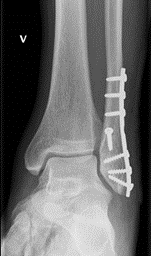

Ankelbrudd: Behandling med operasjon

De fleste ankelbrudd kan behandles uten operasjon. Hvis bruddet er ustabilt, er det ofte aktuelt å operere med plate.